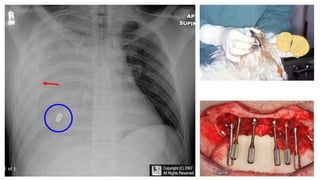

The document presents a chest X-ray examination summary by Ninian Peckitt, detailing various respiratory conditions including tracheal deviation, pleural effusions, and lung collapses. Findings suggest thoracic trauma and hyperinflation in the lungs. Additionally, it includes links to medical products and their pricing.